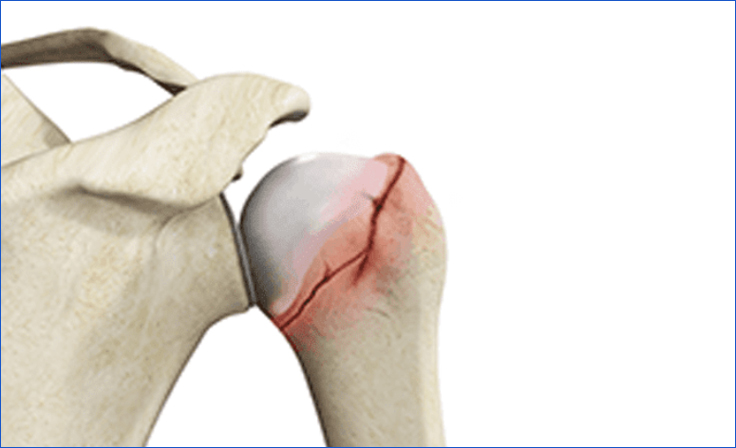

Rotator Cuff Tear

The rotator cuff is a group of muscles and tendons that stabilize the shoulder. Tears can occur due to injury, overuse, or degeneration.

• Icon Symptoms: Shoulder pain (especially at night), weakness, difficulty lifting the arm, and a cracking sensation with movement

• Icon Treatment: Rest, physical therapy, anti-inflammatory medications, corticosteroid injections, PRP injection or surgical repair for complete tears